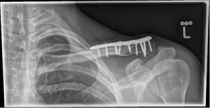

Acromioclavicular (lateral clavicular fracture), should be treated surgically, as a conservative therapy often leads to the formation of a so-called pseudarthrosis. Various implants are available, such as the hook plate and an anatomically preformed angular stable lateral clavicle plate.

Pictures: Here, an angle-stable plate was used to supply the clavicle fracture near the shoulder joint. This plate makes it possible to anchor many screws in the fragment and thus obtain a good stabilization.